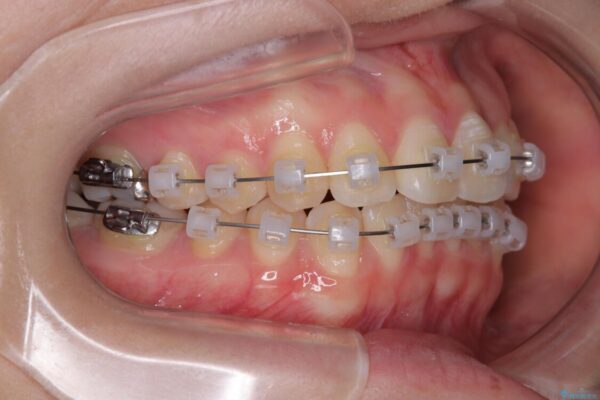

治療途中

• 前歯のねじれ・ガタガタを10か月で改善!20代女性の矯正治療|クリアブラケットでむし歯になりにくい歯並びへ改善 治療途中画像

診察の結果、上下の前歯部に**叢生(そうせい/歯のガタガタ・重なり)**が認められました。

特に上の前歯にはねじれや重なりがあり、審美的にも清掃性にも影響している状態でした。

治療方法としては、装置の目立ちにくさと費用面のバランスを考慮して、プラスチック製のクリアブラケットとメタルワイヤーを組み合わせた矯正装置を使用することにしました。